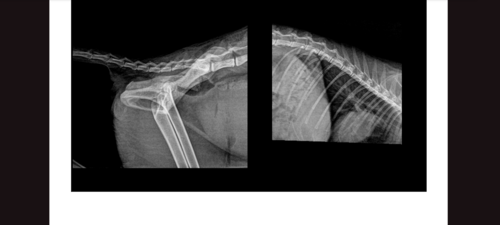

Olá eu sou a Maggie, estava correndo de outro gatinho que estava me incomodando no muro da minha casa, sofri um acidente pois cai do muro e estou precisando urgentemente de uma cirurgia para realinhar minha coluna que está com fratura Interna, já não consigo fazer minhas necessidades sozinha, perdi os movimentos das minhas perninhas traseiras, e todos os dias tomo tramadol de 12h em 12h para não sentir dor, já não posso fazer o que eu amo que correr e nem brincar mais😔